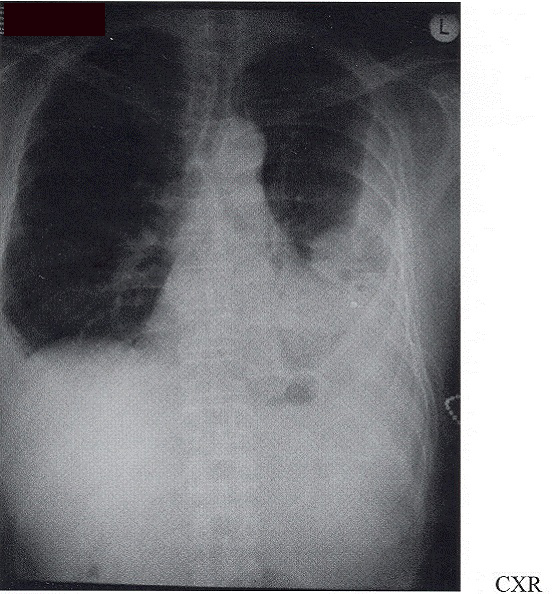

He was a chinese medicine trader requiring frequent travel between Hong Kong and China. His last flight travel was in early August, 2001 to Hainan Island. CXR showed bilateral pleural effusion with a left lung mass and he was admitted to Hong Kong Sanatorium and Hospital (HKSH) for further investigation.

Software: Microsoft Office

Pyothorax associated lymphoma was first reported by Japanese in 1987. Iuchi et al reported 3 out of 134 patients developed pleural lymphoma with history of chronic pyothorax at a chest hospital in Osaka from 1971 to 19851.Aozasa thus carried out a nation-wide study in Japan during 1987 to 1988 and 37 patients with pleural lymphoma were studied 2. The age at diagnosis was between 46 to 81 years old (mean 63) with male to female ratio of 5.2 to 1. All patients had greater than 20 years history of chronic pyothorax as a result of artifical pneumothorax for either pulmonary tuberculosis or tuberculous pleuritis. The commonest presenting symptoms were productive cough, dyspnoea and chest pain. Thirty-five percent of lung masses were reviewed by CXR while 77% by CT. Histologically, majority (85%) were B-cell type. From these finding, pyothorax-associated lymphoma (PAL) was proposed. Obsawa later detected EBV genome in over 80% of PALpatients 3.